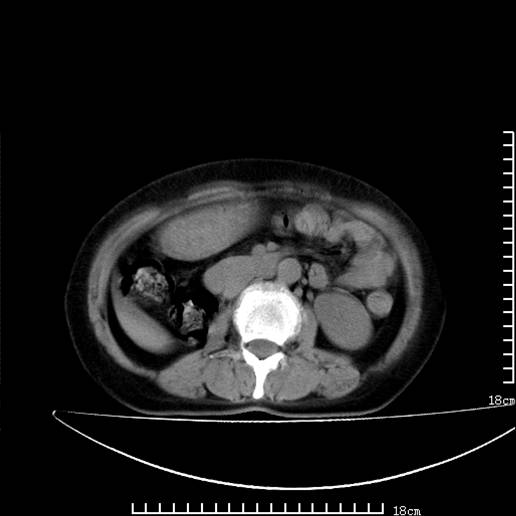

以下是引用pujunzhi在2008-5-30 15:31:00的发言:[br]异位肾—盆腔肾。当看到肾窝无肾脏时,要想到孤立肾和异位肾,异位肾最常见是盆腔肾,偶见胸腔,易误认为肺占位,只要想到就不会漏诊。建议增强扫描。